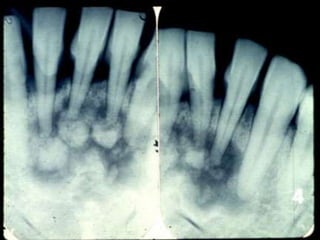

 Radiographic findings

 Pulpless, nonvital tooth

 Small well-defined periapical radiolucency

Radicular (Periapical) Cyst Most common (65%)  Epithelial cell rests of Malassez  Response to inflammation  Radiographic findings  Pulpless, nonvital tooth  Small well-defined periapical radiolucency  Histology  Treatment – extraction, root canal